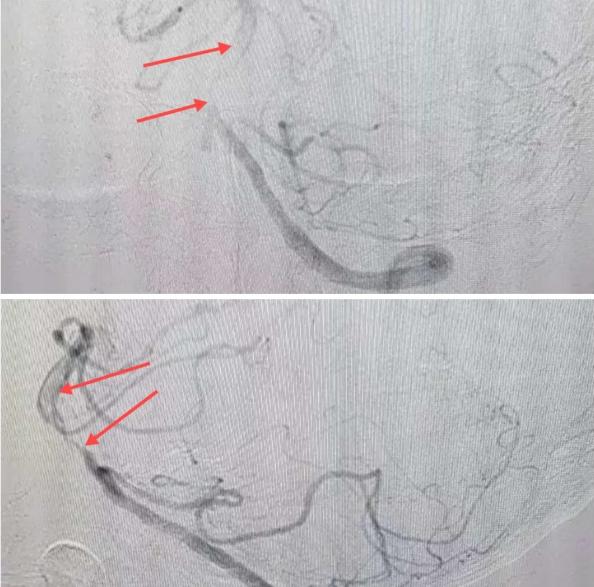

在經(jīng)造影后,主刀醫(yī)生腦一科副主任楊慶堂發(fā)現(xiàn)患者基底動脈下段重度狹窄且狹窄段以遠(yuǎn)有大負(fù)荷血栓,其狹窄處考慮為動脈夾層,手術(shù)難度及風(fēng)險(xiǎn)較大。楊慶堂副主任在彭壯副主任醫(yī)師的協(xié)助下運(yùn)用spaceman(太空人)技術(shù),中間導(dǎo)管抵近血栓抽吸配合支架拉栓,成功開通血管。再次造影可見基底動脈管腔明顯增寬,遠(yuǎn)端血管顯影良好,且等待20分鐘后造影仍顯示血流通暢。楊慶堂副主任考慮到本次手術(shù)時(shí)間不宜過長,現(xiàn)患者基底動脈及分支前向血流維持良好,給予其抗栓藥物應(yīng)用后結(jié)束手術(shù),并建議患者3個(gè)月后復(fù)查造影,明確其基底動脈夾層情況。

造影可見血管夾層和大量血栓形成

取栓后血管管腔增寬,前向血流良好